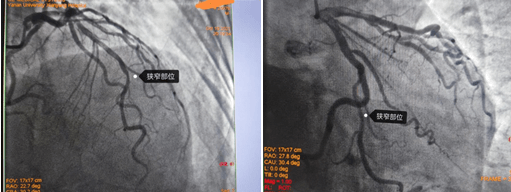

造影結(jié)果右冠多處狹窄約70-90%,左冠也是多處70-80%狹窄;對于這樣一個結(jié)果,是這些狹窄造成的胸悶、心悸嗎?這些病變需不需要都給予介入處理呢?一根血管植入支架還是三根血管都需要植入支架?心內(nèi)九科崔旭輝主任帶領(lǐng)介入醫(yī)生團(tuán)隊(duì)討論后,決定進(jìn)行RFR檢查給出一個明確的答案。所以經(jīng)過與患者及其家屬溝通后選擇進(jìn)行RFR檢測,結(jié)果如下圖:

RFR靜息全周期比值,是最新的評價冠狀動脈的功能學(xué)指標(biāo)。相比傳統(tǒng)的FFR檢查,RFR檢查無需使用最大充血藥物,避免了患者不適,更簡單、安全,而且手術(shù)時間更短,效率更高。通過RFR指導(dǎo)冠狀動脈介入治療,可以改善患者預(yù)后,節(jié)約醫(yī)療費(fèi)用。崔旭輝介入團(tuán)隊(duì)在心導(dǎo)管室技師的協(xié)助下,半小時內(nèi)完成左右冠脈內(nèi)RFR檢查,結(jié)果分別是:0.92,0.97,0.96;根據(jù)客觀的檢查結(jié)果,患者三支血管都不需要植入支架,馬先生一家高興地放下了思想包袱,開心回到病房,繼續(xù)藥物治療。